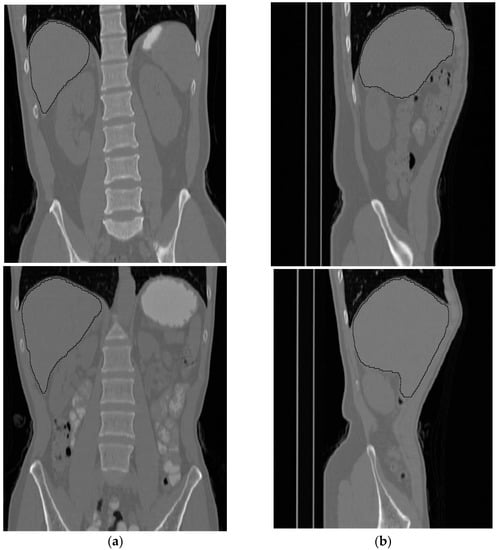

The volumetric information for the total abdomen fat, SF, and VF does not provide realistic information about obesity due to the variation in the sizes of people. Therefore, the following ratios were used as an indication of obesity. For each subject, CT slices between the first and fifth lumbar vertebrae (L1–L5) were used. Figure 12 shows two samples that highlight the area where the CT slices were selected from. The region of interest is bounded by the two white lines.

Figure 12. Two samples show the area where the CT slices are selected from. (a) Front view, (b) side view.